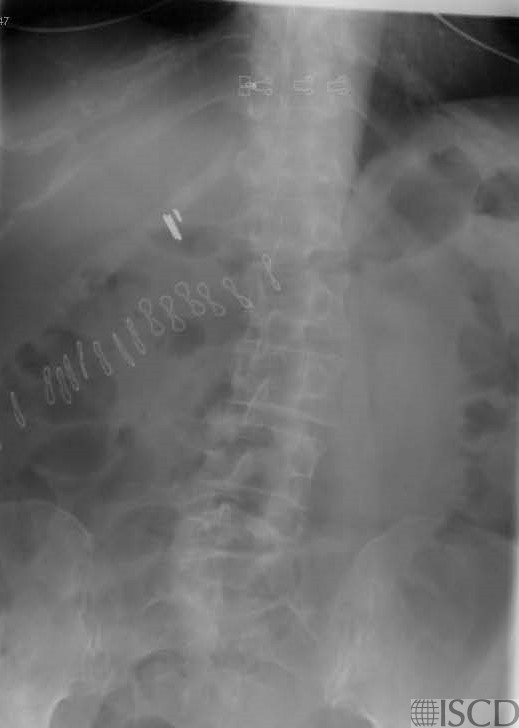

This is the accompanying radiograph which shows the clips and the clips causing the black hole-type artifact

The Hologic lumbar spine image shows surgical clips latera to L2-L3 on the right clips over L2. There is a prominent black hole-type artifact lateral to L1-L2 on the right on the dual energy scan. The accompanying radiograph also shows the internal artifacts.